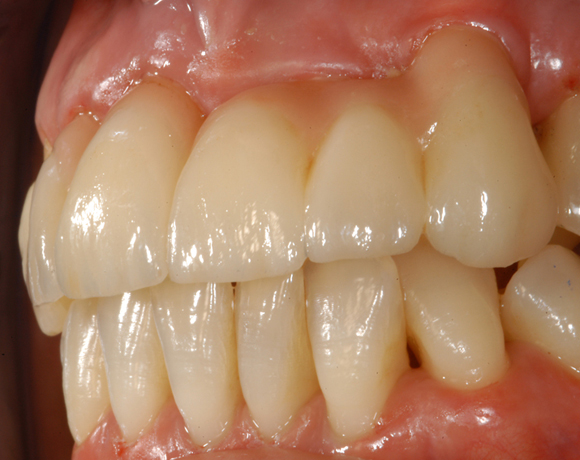

vollkeramischen Brücke versorgt. da die Patientin eine metallfreie Versorgung wünschte,

wurden Zeramex C Implantate gewählt, auch der Zahn 22 wurde mit einer vollkeramischen

Krone versorgt.